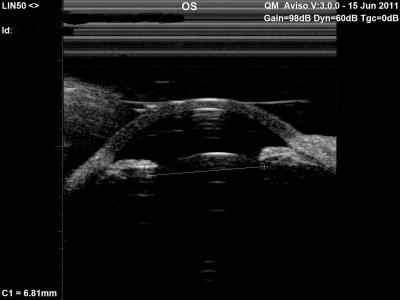

Cornea and Lens Diameter Relationship in Children

Figure 1: Crystalline lens and anterior segment axial cross-section as captured by the Quantel Aviso UBM 50Mhz probe